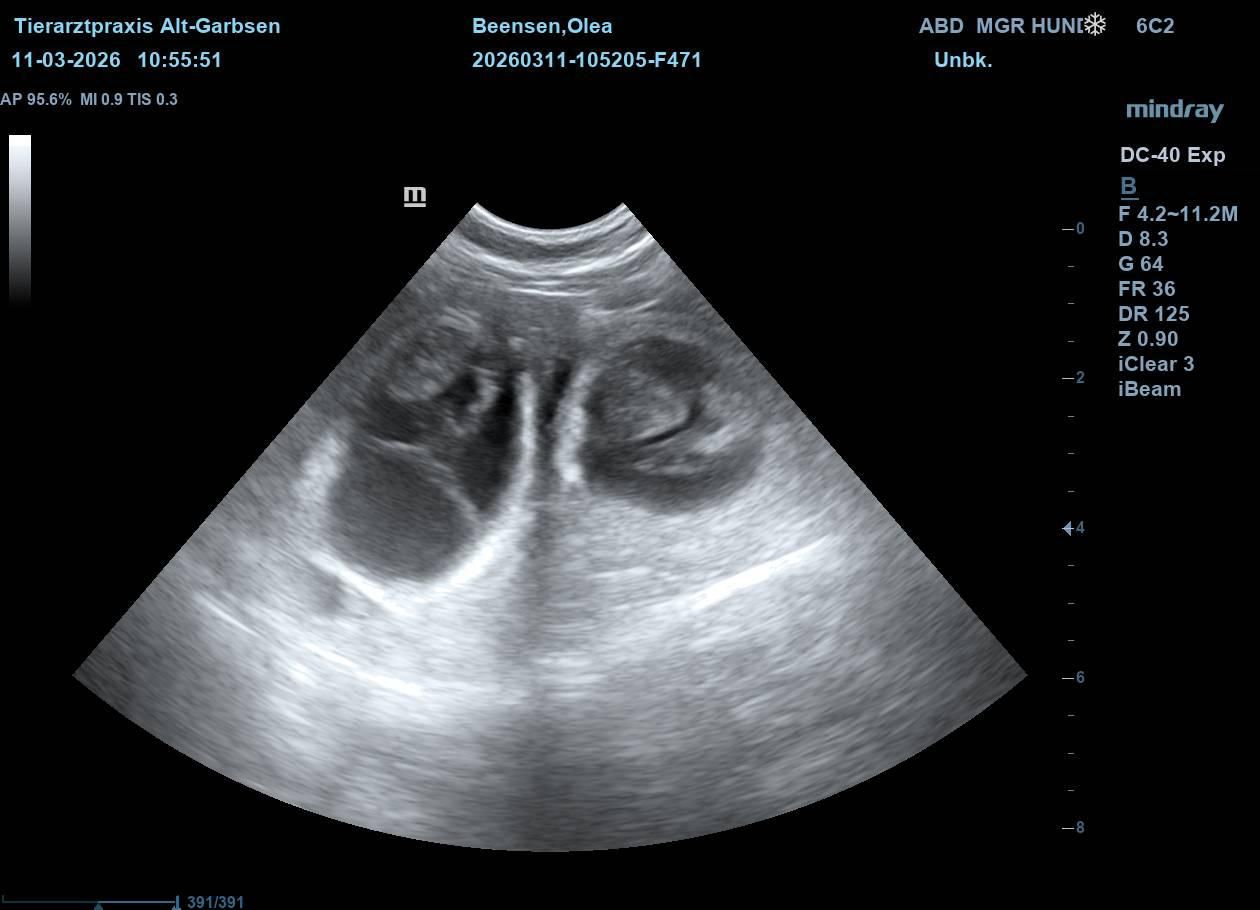

Update vom 11.03.2026:

Heute war ein ganz besonderer Tag. Olea war zum Ultraschall. Schon seit einigen Tagen hatten ihre Besitzer das Gefühl, dass sich etwas verändert hat. Sie war ruhiger und anhänglicher geworden - und ihr Bäuchlein schien sich leicht zu runden.

Beim Ultraschall war es dann eindeutig. Kleine, deutlich erkennbare Welpen. Auf dem Bildschirm waren mehrere winzige Herzschläge zu sehen. Freude, Aufregung und Ehrfurcht - alles zusammen stellte sich bei den Besitzern ein. Olea lag ganz entspannt - als wüsste sie, dass in dem Moment etwas ganz Wundervolles passiert. Jetzt beginnt die spannende Zeit der Vorbereitung. In den nächsten Wochen wird alles für die Ankunft der kleinen "vom Jademeer´chen" vorbereitet. Nicht mehr lange.....